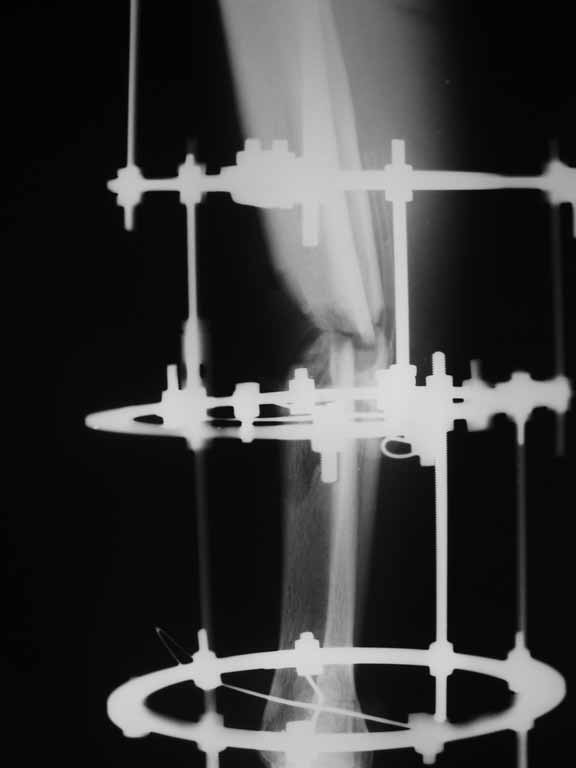

Здравствуйте,уважаемые коллеги! Прошу помочь с тактикой дальнейшего лечения.26.09.11г в

отделение поступил молодой человек 18 лет после ДТП: пассажир мотоцикла. Диагноз:

сочетанная травма головы и правой голени. ЗЧМТ с ушибом головного мозга лёгкой степени,

открытый перелом обеих костей правой голени в средней трети голени со смещением с дефектом

диафиза дистального отломка. Рана голени 4х2см по передне-внутренней поверхности.

Ургентно произведена ПХО раны и ЧКО голени аппаратом внешней фиксации. В настоящее время

состояние больного удовлетворительное, регресс неврологической симптоматики, на месте

полученной раны имеется поверхностная гранулирующая рана 1,5х 0,7см. Стал вопрос: что

делать дальше, как компенсировать дефект? Наши варианты: внедрение дистального отломка в

костно-мозговой проксимального, резекция дистального отломка с последующим замещением

костным регенератом, блокирующий остеосинтез ...или?